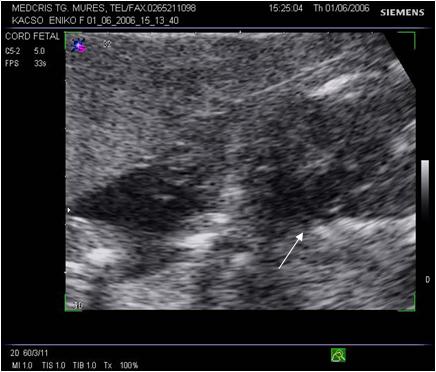

Fig. nr.257 Mielomeningocel occipital sarcina 22 sapt..

Fig. nr. 258. Defectul de inchidere a arcurilor vertebrale din figura anterioara, prezentat in sectiune transversala.( Sageta )